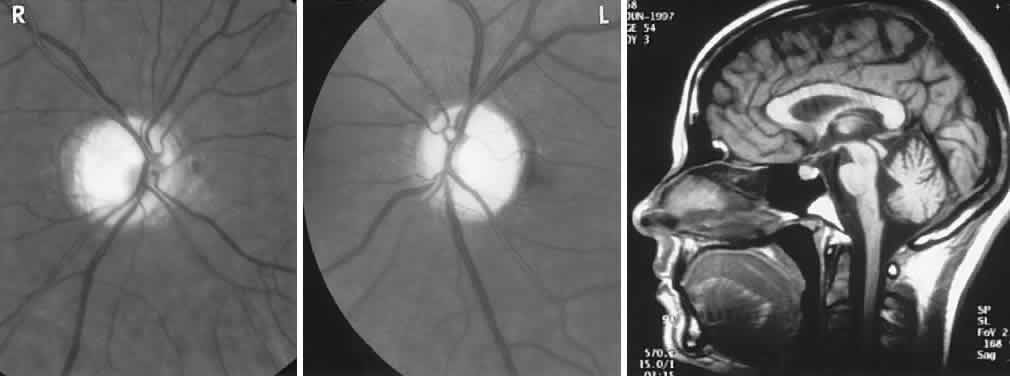

CONGENITAL HAMARTOMA SYNDROMES

The “neurophakomatoses” are a diverse group of disorders nosologically related by the presence of hamartomatous lesions, and, indeed, the term “hereditary hamartomatosis” is a more accurate description. However, whereas neurofibromatosis, tuberous sclerosis, and von Hippel-Lindau disease are transmitted with irregular dominance and considerable variation in penetrance, no hereditary basis of Sturge-Weber or angio-osteohypertrophy (Klippel-Trenaunay-Weber) syndrome has been established.

A hamartoma is a tumor of anomalous origin composed of elements normally present in the tissue in which it originates and with a limited capacity for proliferation. The following tumors may be classified as hamartomas: (1) in neurofibromatosis: optic gliomas (see Chapter 6), neurofibromas, and ganglioneuromas; (2) in tuberous sclerosis: retinal and cerebral astrocytomas, cutaneous angiofibromas (“adenoma sebaceum”), rhabdomyomas, and leiomyomas; (3) in von Hippel-Lindau disease: hemangioblastomas of the cerebellum and retina (including optic nerve head) and renal hypernephromas or cysts; (4) in Sturge-Weber disease: facial and choroidal cavernous hemangiomas and meningeal angiomatous malformations; and (5) in Klippel-Trenaunay-Weber syndrome: cutaneous nevi, visceral and limb hemangiomas, and orbitofacial venous varices.

If all disorders with neurocutaneous manifestations are considered, the term phakomatoses (Greek, phakos, “spot,” “birthmark”) is appropriate, and the catalog of “related” disorders becomes cumbersome. “The Phakomatoses,” Volume 14 of Vinken and Bruyn's Handbook of Clinical Neurology, is extraordinarily complete and serves as a source of detailed clinical descriptions of these diseases.146 Syndromes characterized by vascular hamartomas, that is, retinal-cerebellar angiomatosis (von Hippel-Lindau), and other angiomatous malformations, are discussed in Volume 2, Chapter 17.